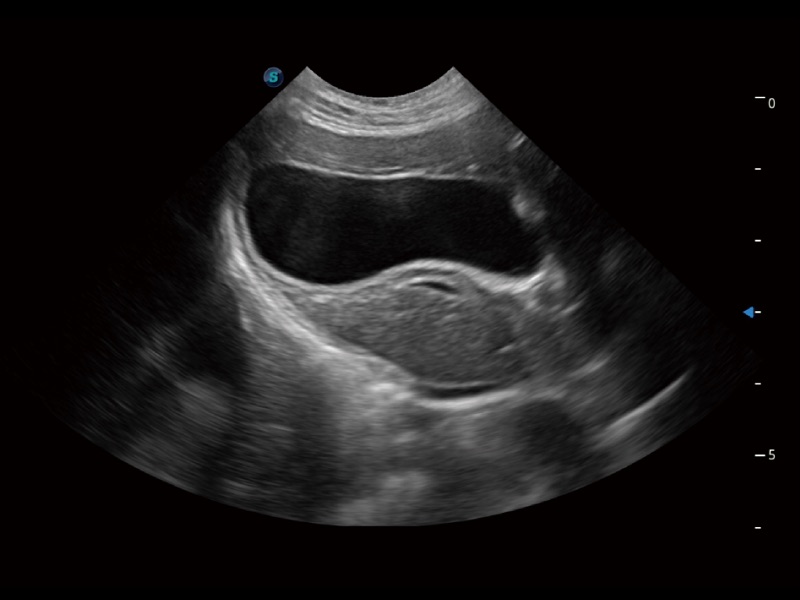

ProPet 70 进一步提升了微米成像算法,更加注重对基础原始图像的还原和保留,在有效减少斑点噪声、增强组织边界显示的同时,避免过度优化丟失真实的解剖信息。

为精细结构及组织边缘提供高清晰度的图像和更大的成像视野。帮助减轻医生的用眼疲劳,快速精准获得测量的数据。